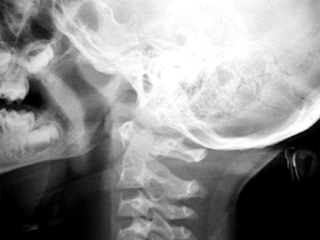

Năm 1970, bác sĩ Robert White đă cấy ghép thành công đầu của của loài khỉ rhesus vào cơ thể của một con rhesus khác. Nhưng ở thời điểm đó các nhà khoa học đă không thể nối đầu với tủy sống làm con vật bị tê liệt dưới điểm cấy ghép.

Theo trang tin UPI, tiến sĩ Sergio Canavero, một thành viên của Nhóm nghiên cứu nâng cao về thần kinh, vừa xuất bản một báo cáo khoa học cho biết giờ đă có công nghệ có thể cấy ghép đầu của một người này vào cơ thể của một người khác.

Phần lớn quy tŕnh cấy ghép lần này được giữ nguyên giống thử nghiệm cũ. Đầu được cấy ghép được ướp lạnh từ 12-15 độ C. Sau đó các bác sĩ phẫu thuật sẽ có 1 tiếng đồng hồ để cùng lúc cắt bỏ 2 đầu và cấy ghép với hệ thống tuần hoàn của cơ thể nhận. Trong suốt quá tŕnh cấy ghép, cơ thể hiến phải được ướp lạnh và tim phải hoàn toàn ngừng đập. Khi đầu đă được nối, tim của cơ thể hiến có thể hoạt động trở lại.

Khi đầu được nối lại, các bác sĩ phẫu thuật tiến hành nối tủy sống. Việc này chưa từng được thử nghiệm trên động vật nhưng trong nghiên cứu của ḿnh, Canavero đă chỉ ra là các nhà khoa học đă kết nối có giới hạn tủy sống của loài chuột. Canavero đề xuất cắt dây cột sống bằng một con dao cực sắc và sau đó nối dây cột sống từ đầu sang cơ thể khác. Ông phỏng đoán rằng các loại nhựa như polyethylene glycol (PEG) có thể được dùng để thực hiện sự hợp nhất này. Chi phí cho một ca cấy ghép đầu ước tính khoảng 13 triệu USD.